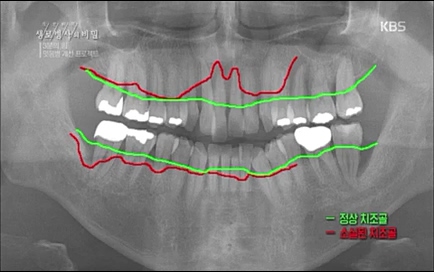

뿌리 끝까지 (잇몸)뼈가 굉장히 많이 녹아있고